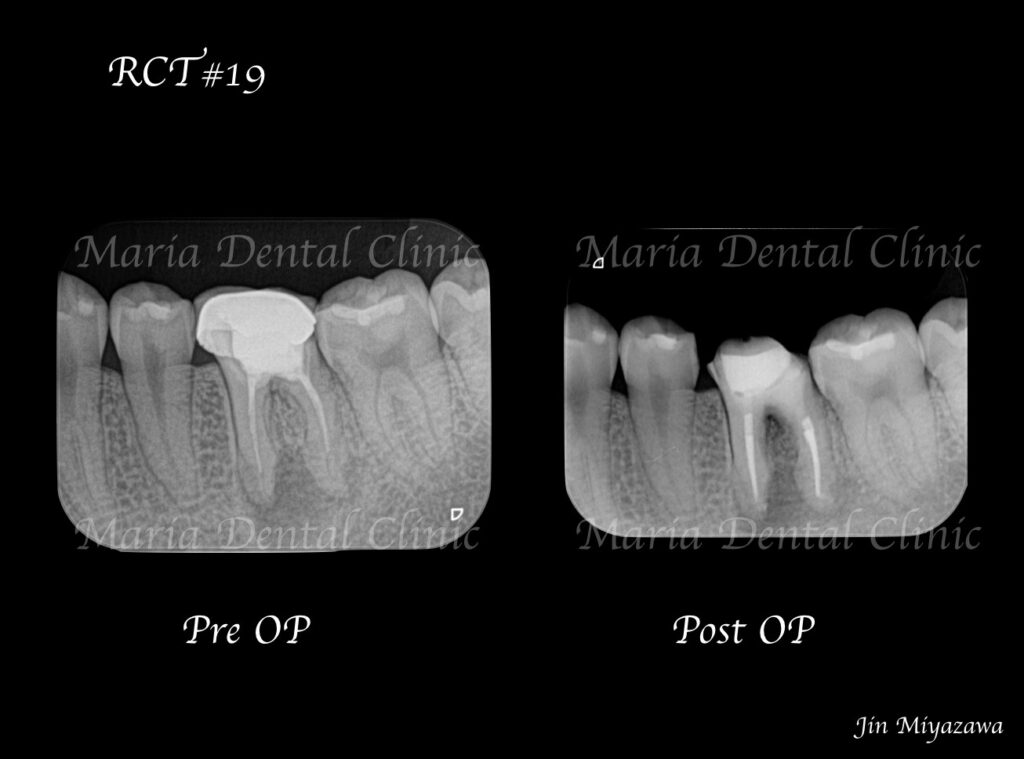

歯肉が腫れと痛みを訴え来院された患者様です。症状、レントゲン、ポケット診査より根尖性歯周炎と診断。 診査時には触ることでの痛み、限局的な歯周ポケットを確認しました。

顕微鏡下にて、軟化象牙質(虫歯)や根管内充填物を綺麗に除去し、貼薬を1週間行いました。

1週間後、痛みと腫れは消失しました。

今回の症例は、左下奥歯が腫れたことを主訴に来院された患者様のケースをご紹介しました。